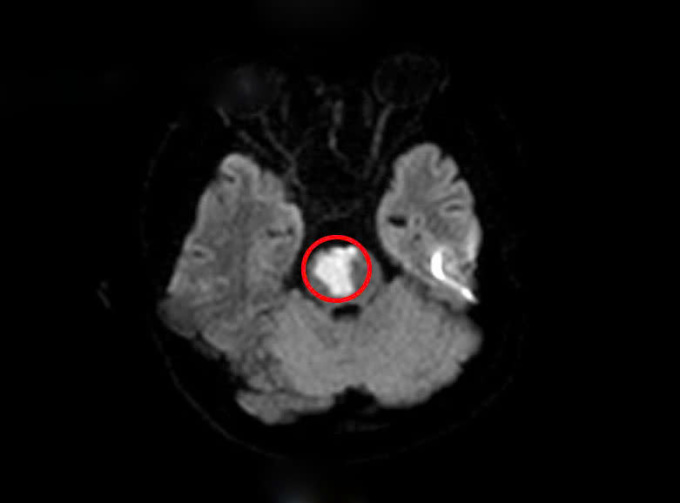

Kết quả chụp MRI sọ não bệnh nhân phát hiện khối nhồi máu tiểu não,cầu não do tắc động mạch thân nền. Xét nghiệm máu có rối loạn lipid máu,một yếu tố nguy cơ dẫn đến các vấn đề tim mạch và mạch máu não. Người bệnh được phát hiện bất thường trong hệ gene làm tăng nguy cơ tạo huyết khối tắc mạch.

Kết quả chụp não phát hiện nhồi máu não. Ảnh: Bệnh viện cung cấp